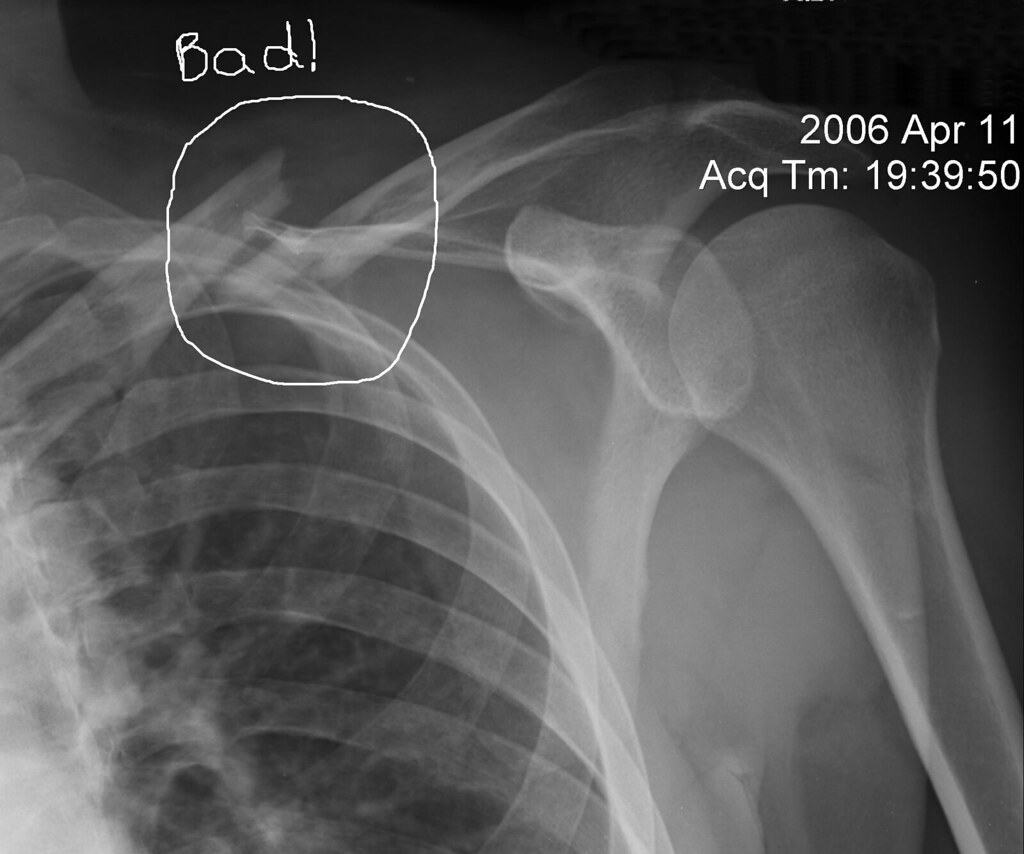

from jrrudzkimd.com

Broken Clavicle, 2 weeks XRay not looking good Training TrainerRoad How Soon After Clavicle Surgery Can I Cycle As a rule of thumb, if you choose to have surgery you can expect your recovery to be six weeks quicker than someone who leaves the fracture to heal naturally. Professional cyclists have a contract to uphold and. Most clavicle fractures heal after about 6 to 12 weeks. Resuming riding can occur anywhere from 3 to 12 weeks after a. How Soon After Clavicle Surgery Can I Cycle.